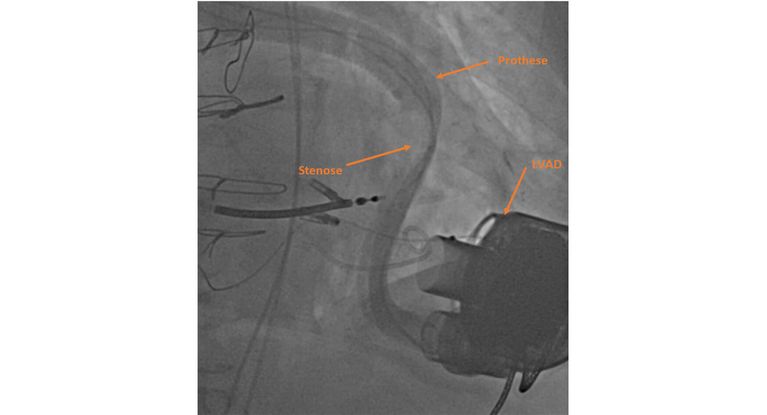

Angiographie: vor Stenting der Prothese sieht man eine Einengung im Verlauf der Prothese zur Aorta.